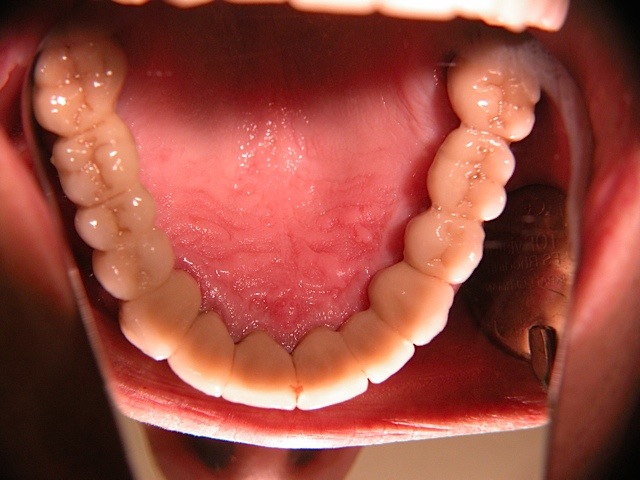

Die folgenden Patientenfälle sollen Ihnen einen Einblick in die Möglichkeiten der modernen Implantation geben.

Sofort-Implantation: